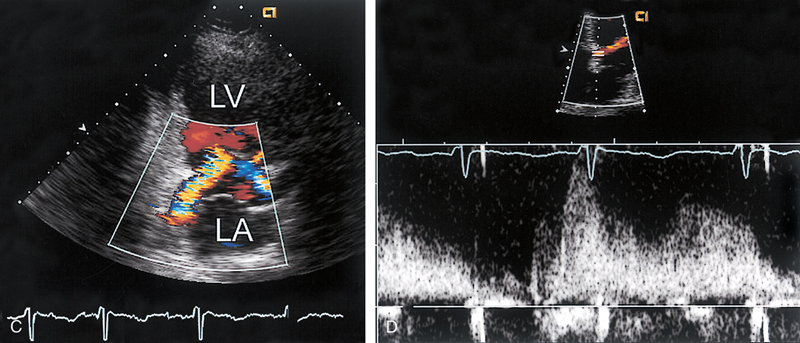

فحوصات تشخيصية لبعض امراض القلب والشرايين التاجية